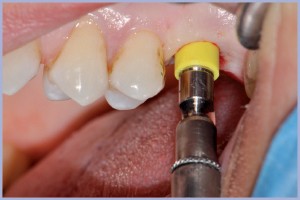

- Fig. 3 – Inserimento di impianto Exacone® Max Stability Ø 4,5 mm in tecnica flapless